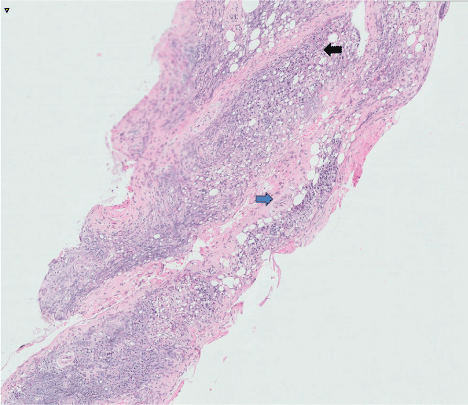

Figure 2: Histology showing lymphoplasmacytic infiltrate [black arrow] and fibrosis [blue arrow].